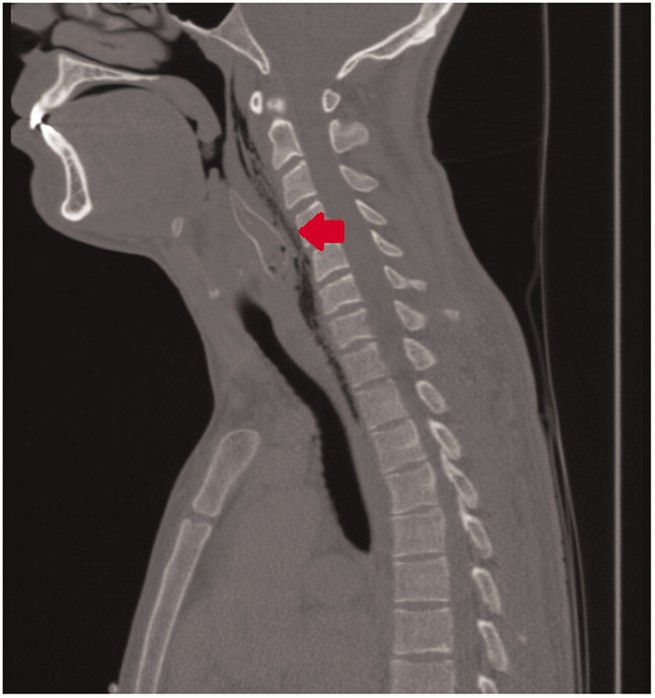

Ảnh chụp CT-scan vùng đầu cổ cho thấy một dị vật (mũi tên) dài ± 5 cm và ngang 1,5 cm ở hầu họng chàng thanh niên, ở thời điểm các bác sĩ chưa biết nó là một con cá.

Trở lại với chàng thanh niên người Hà Lan đã nuốt con cá chuột. Các bác sĩ cuối cùng đã phải gây mê cho anh, đặt ống nội khí quản và dùng ống nội soi để tìm con cá trong hầu họng của anh ấy.